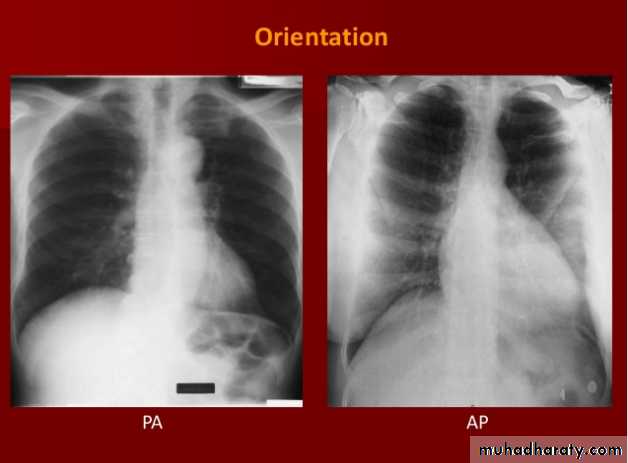

Routine CXR: is PA known as frontal view with optional lateral view.

Both should exposed in full insp. And patient in upright position.Films taken in exp. Are difficult to interpret because:

• 1- hazy lung base.

• 2- heart shadow increase in size.

8- assess technical quality of the film: correctly exposed routine PA CXR is one in which the ribs and spine behind the heart can be identified but lung not overexposed.straight film is one where the medial ends of clavicles are equidistant from thoracic verteb.